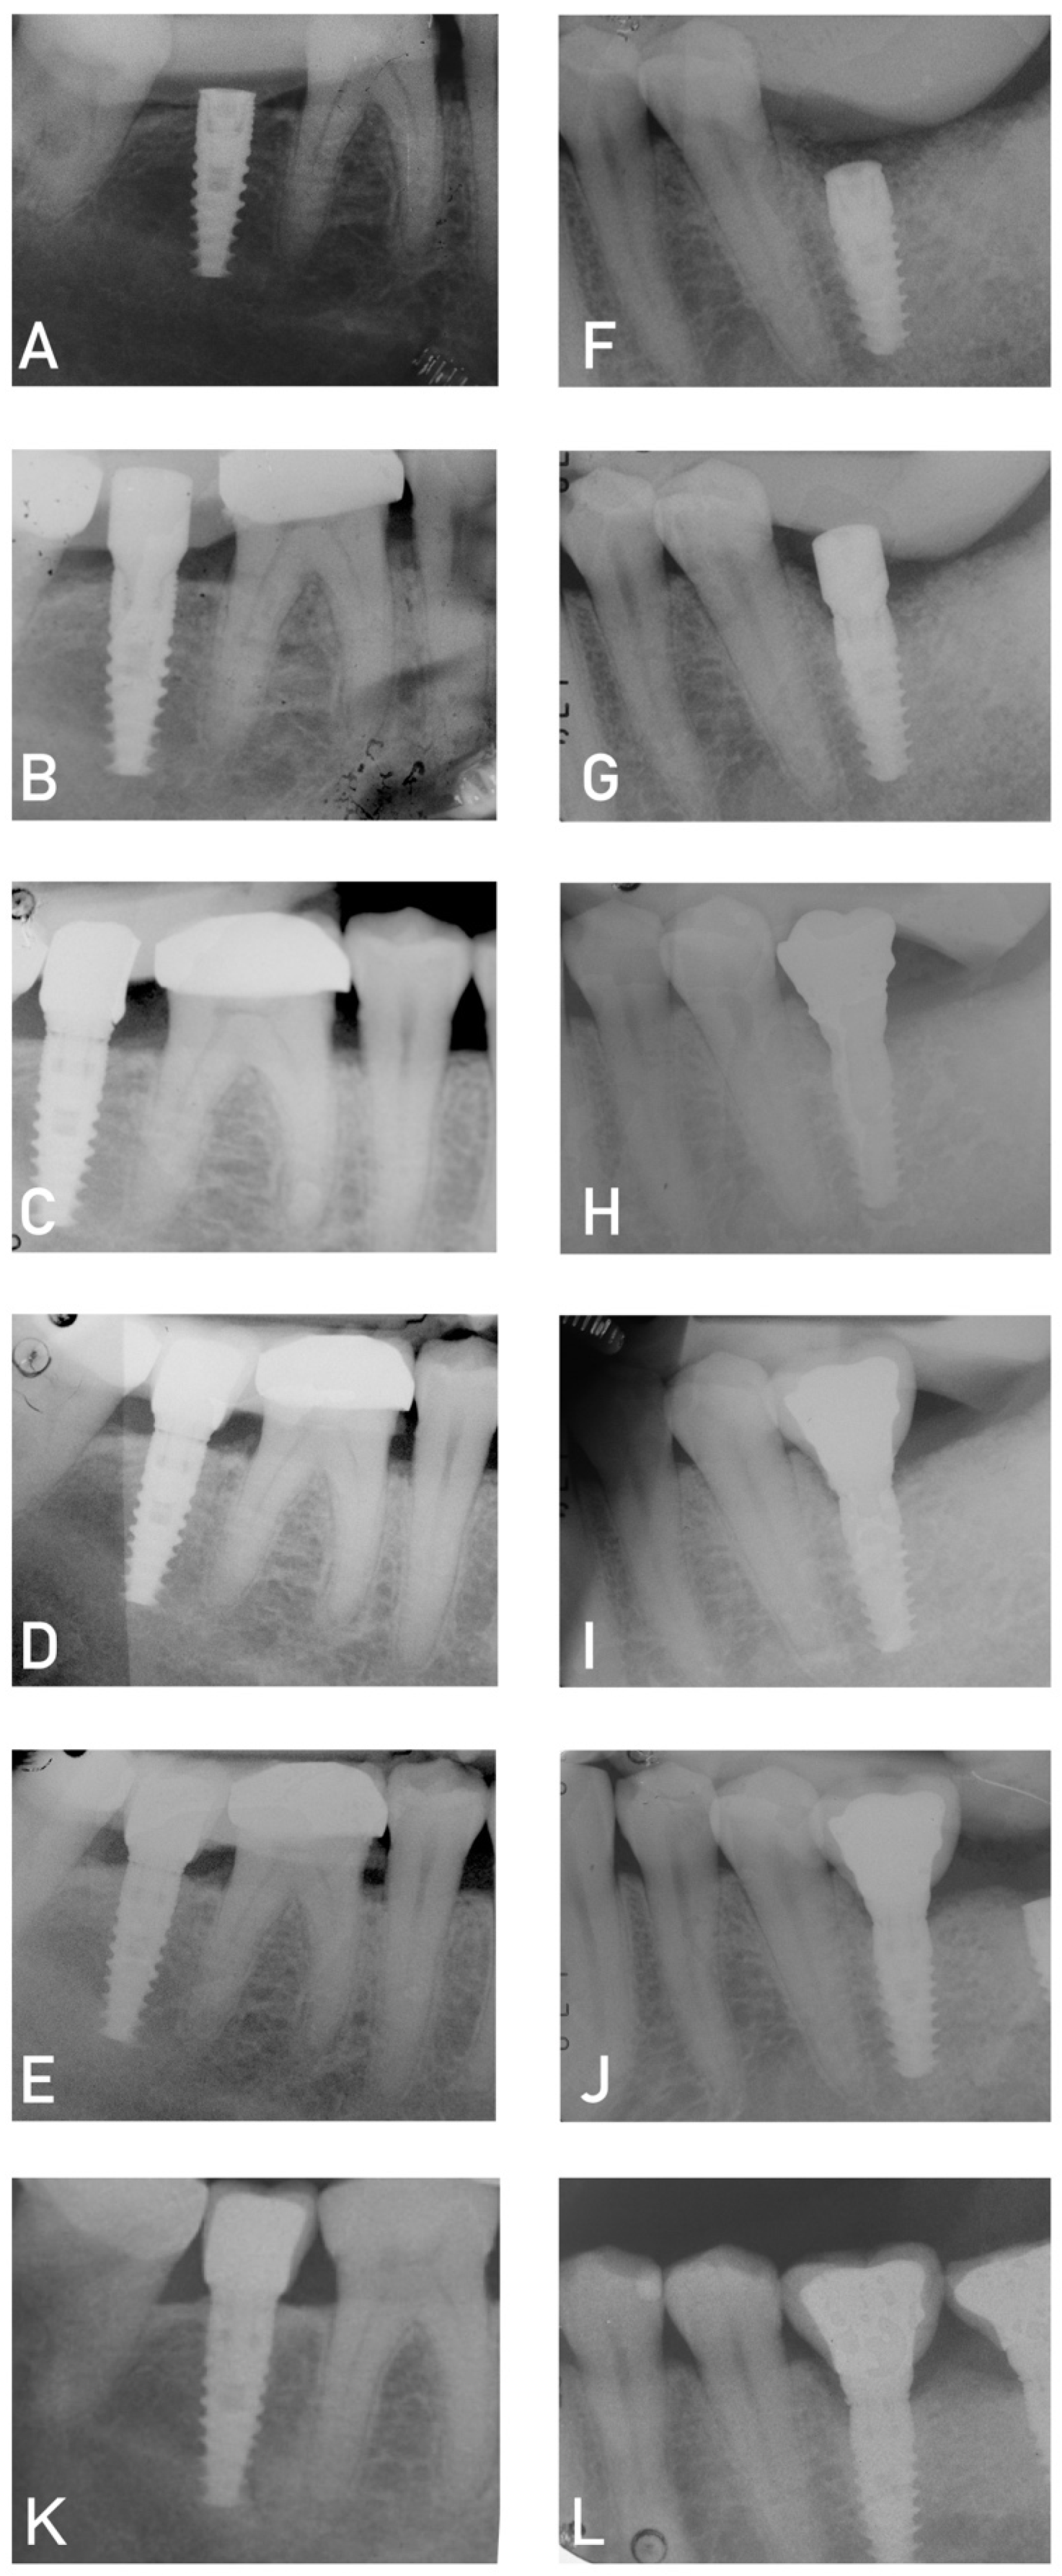

- Periapical X-ray;